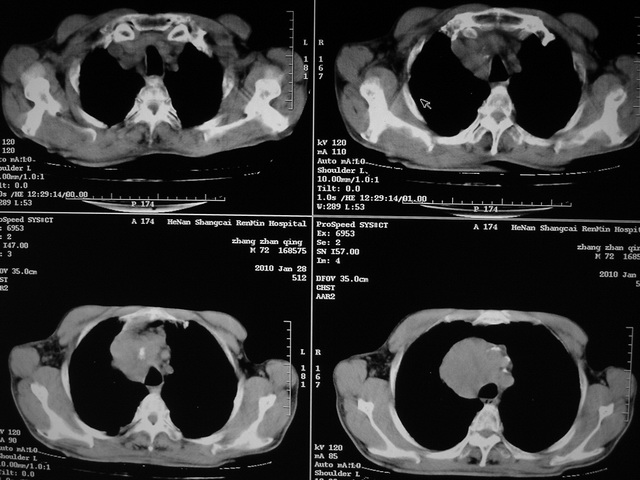

xx m 72岁农民 右侧胸痛6月余,咳嗽,无发热、咯血等

右下周围型肺癌,并右肺门、纵膈淋巴结、内乳淋巴结转移,右胸膜转移累及前胸壁。鉴别:脓肿、tb、淋巴瘤。病理类型可能为大细胞型。

这个病人有点复杂了,上纵隔像是占位,右肺下叶见壁光整厚壁空洞加液平,像是肺脓肿,中叶病灶牵涉到胸膜及胸壁,形态看像是炎性病变,总之不能除外恶性病变,还是穿刺或增强后再说。

支持 右肺下叶周围型肺癌并右肺门、纵膈淋巴结、内乳淋巴结转移,右胸膜转移累及前胸壁。